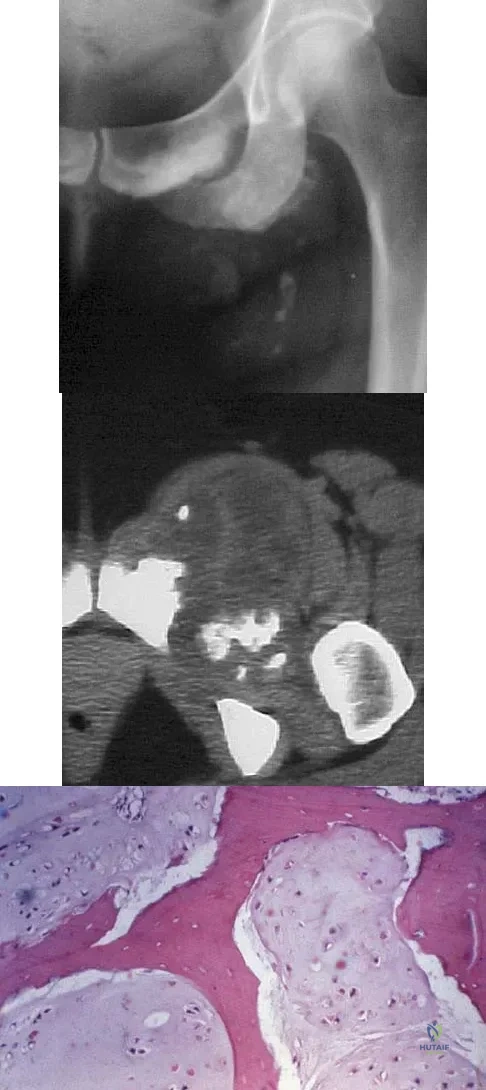

A 43-year-old woman has an enlarging mass in the left groin. A radiograph, CT scan, and a biopsy specimen are shown in Figures 42a through 42c. Treatment should consist of

Explanation